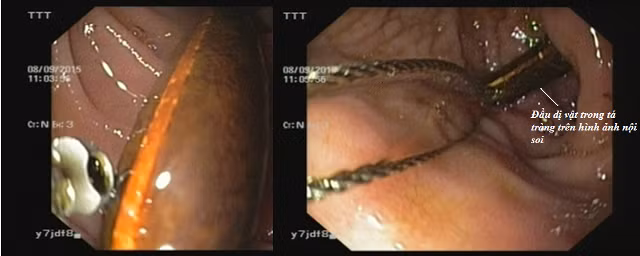

| Hình ảnh nội soi quá trình phát hiện và đưa dị vật ra ngoài. |

Kết quả bất ngờ khi soi tá tràng, bên cạnh niêm mạc vùng hang vị và hành tá tràng xung huyết, bác sĩ còn phát hiện đầu một vật lạ, hình ống bắt đầu từ DI tá tràng kéo dài đến đoạn đầu DIII tá tràng. Xem xét kĩ hình ảnh nội soi, bằng kinh nghiệm dày dạn trong nội soi tiêu hóa, nhanh chóng xác định là một dị vật chứ không phải là xác giun, BS. Cường đã quyết định sử dụng kĩ thuật gắp dị vật qua nội soi bằng thòng lọng. Do dị vật có đặc điểm là một ống hình trụ dài, không thể cố định chắc chắn dị vật mà chỉ có thể cố định một phía của dị vật, từ đó xuất hiện các nguy cơ chảy máu đường tiêu hóa do sang chấn của dị vật trong quá trình đưa ra ngoài, dị vật rơi vào khí quản hay thủ thuật thất bại phải thực hiện lại nhiều lần…